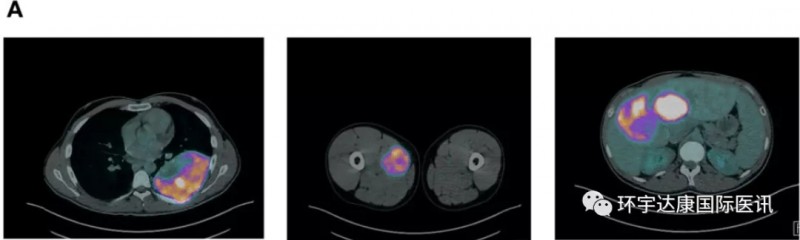

软组织肉瘤腹部隆突性皮肤纤维肉瘤新药Larotrectinib(拉罗替尼)让全身转移的患者肿瘤7天消退软组织肉瘤是间充质来源的罕见恶性肿瘤,约占成人癌症的 1%,虽然和肺癌,乳腺癌相比并不常见,但是这是一种异质性极强的复杂肿瘤,目前已知的亚型超过了100种,每一种都具有不同的临床表现。不管是罹患哪一种,晚期患者临床上的治疗方案都非常有限。手术后八年全身转移复

肉瘤靶向治疗,肉瘤靶向药物拉罗替尼挽救手术、放化疗、靶向无效陷入绝境的患者软组织肉瘤是间充质来源的罕见恶性肿瘤,约占成人癌症的 1%,虽然和肺癌,乳腺癌相比并不常见,但是这是一种异质性极强的复杂肿瘤,目前已知的亚型超过了100种,每一种都具有不同的临床表现。不管是罹患哪一种,晚期患者临床上的治疗方案都非常有限。手术,放化疗,靶向治疗后陷入绝境70岁的M女士,